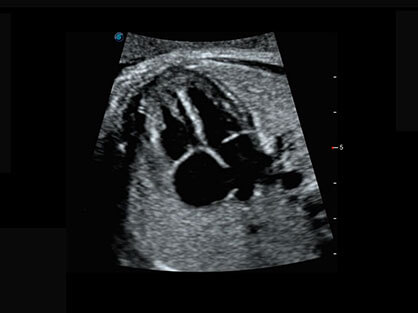

微米成像技术提升了对组织斑点噪声信号的抑制能力,并进一步强化边界信息,从而获得清晰图像。

通过对组织运动信息、血流信号及背景噪声进行准确智能的阈值判定,高效提取出微弱血流信号,获得高灵敏度和空间分辨率的血流图像,为临床提供更加真实和丰富的诊断信息。